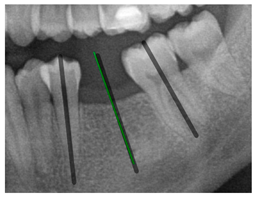

The angle bisector of the two auxiliary lines was then calculated using the angle bisector formula shown in (8), where (, , ) and (, , ) represent the coefficients of the two lines. The resulting internal angle bisector defines the preliminary implant pathway orientation derived by this framework. This bisector represents the most stable implant pathway orientation direction, ensuring that the implant avoids adjacent teeth and critical anatomical structures while maximizing bone–implant contact area. Such orientation enhances osseointegration stability and prevents complications from improper angulation, such as malocclusion or uneven stress distribution. The visualization of this process and the algorithmic design are presented in Figure 8. Finally, the auxiliary pathway generated by the algorithm was compared and overlapped with the implant pathway orientation annotated by dentists on the images to evaluate the predictive capability and accuracy of the model. The overlap results serve as a basis for further model optimization and provide valuable reference information for clinical application.

Figure 8.

Auxiliary lines are derived from adjacent teeth, the blue and yellow line is the result of implant pathway orientation visualization algorithm, and the green is the best implant pathway orientation.

3.3. Comparison with Clinical Ground Truth and AI-Assisted Framework

This subsection presents a comparison between the dentist-defined clinical gold standard and the predictions generated by our AI-assisted framework to evaluate the reliability of implant pathway orientation. The result is shown in Table 10, the preserved DPR validation set was used for verification, and the AI-assisted framework results were overlaid onto the original DPR images to provide a clear visualization. The AI-assisted framework pathways (green lines) were highly consistent with the dentists’ ground-truth annotations (black lines). Quantitatively, the mean squared error (MSE) between the predicted implant direction and the dentists’ planned results was only 1.537° across multiple test images. This minimal deviation validates the proposed system’s technical feasibility. It highlights its clinical potential to provide accurate and stable guidance for implant placement, thereby reducing the risk of misalignment and supporting efficient preoperative orientation.